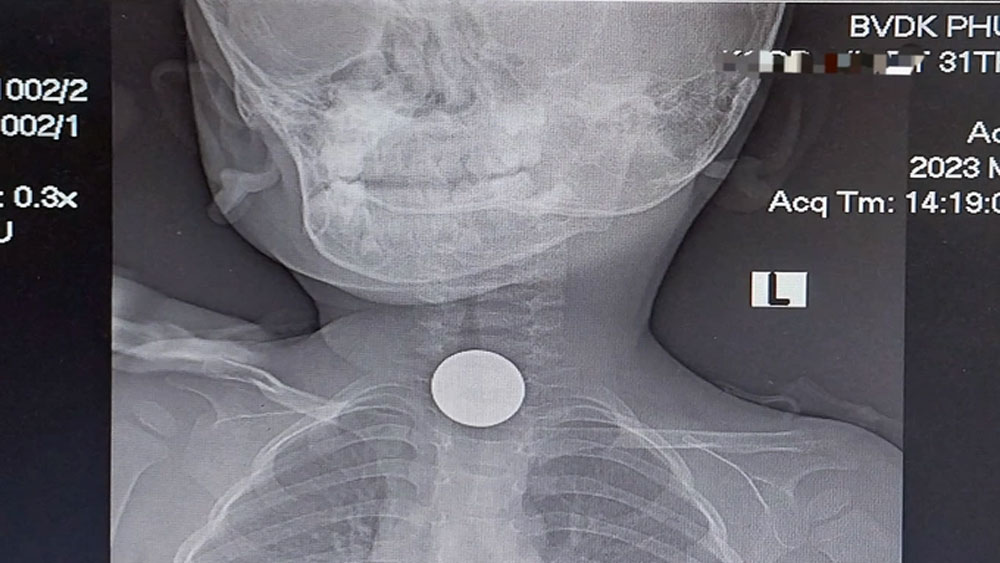

Bệnh nhân ngộ độc botulinum điều trị ở bệnh viện. |

Từ ngày 7 đến 16/3, 10 người ở huyện Phước Sơn bị ngộ độc sau khi ăn cá chép muối chua, trong đó một trường hợp tử vong. Kết quả xét nghiệm cấy mẫu cá muối chua xác định họ bị ngộ độc botulinum. Để điều trị, các bác sĩ Bệnh viện Chợ Rẫy (TP HCM) mang 5 lọ thuốc giải độc đến Quảng Nam hỗ trợ cứu người. Đây là thuốc rất hiếm, thông thường Việt Nam không dự trữ hoặc cả nước chỉ có vài lọ. Ba bệnh nhân nặng nhất được tiêm thuốc giải độc.